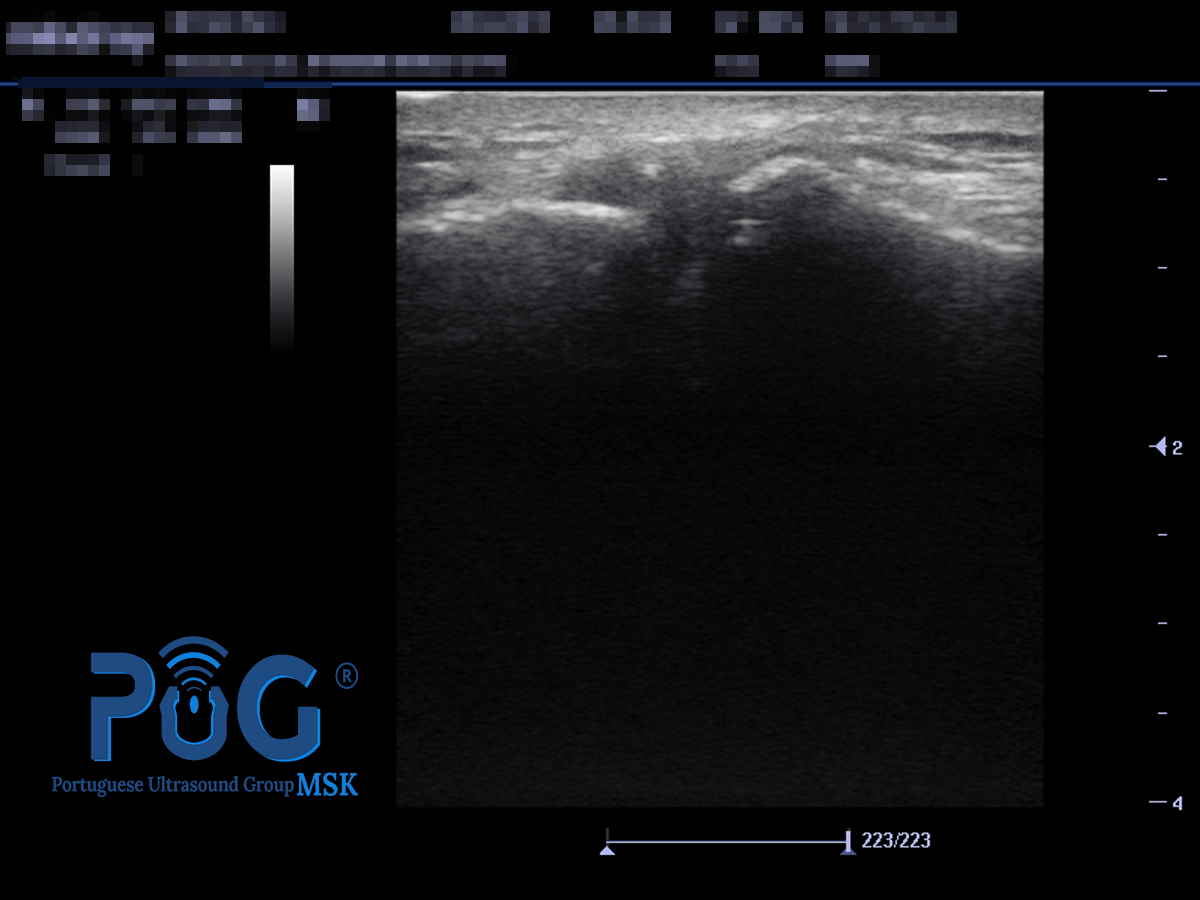

Quando existe uma neoneurovascularização no TA, na avaliação por imagem, podemos identificar a presença de Power Doppler positivo, ou seja, um sinal Doppler activo no lado ventral do TA. A neoneurovascularização pode ser definida como uma proliferação da rede nervosa e sanguínea (gordura de Kager’s), para o interior do tendão. Apesar de não existir uma associação absoluta entre dor e a neoneurovascularização intratendinosa, a evidência científica indica um nível de dor mais elevado em tendões hipervascularizados em comparação com tendões hipovascularizados.